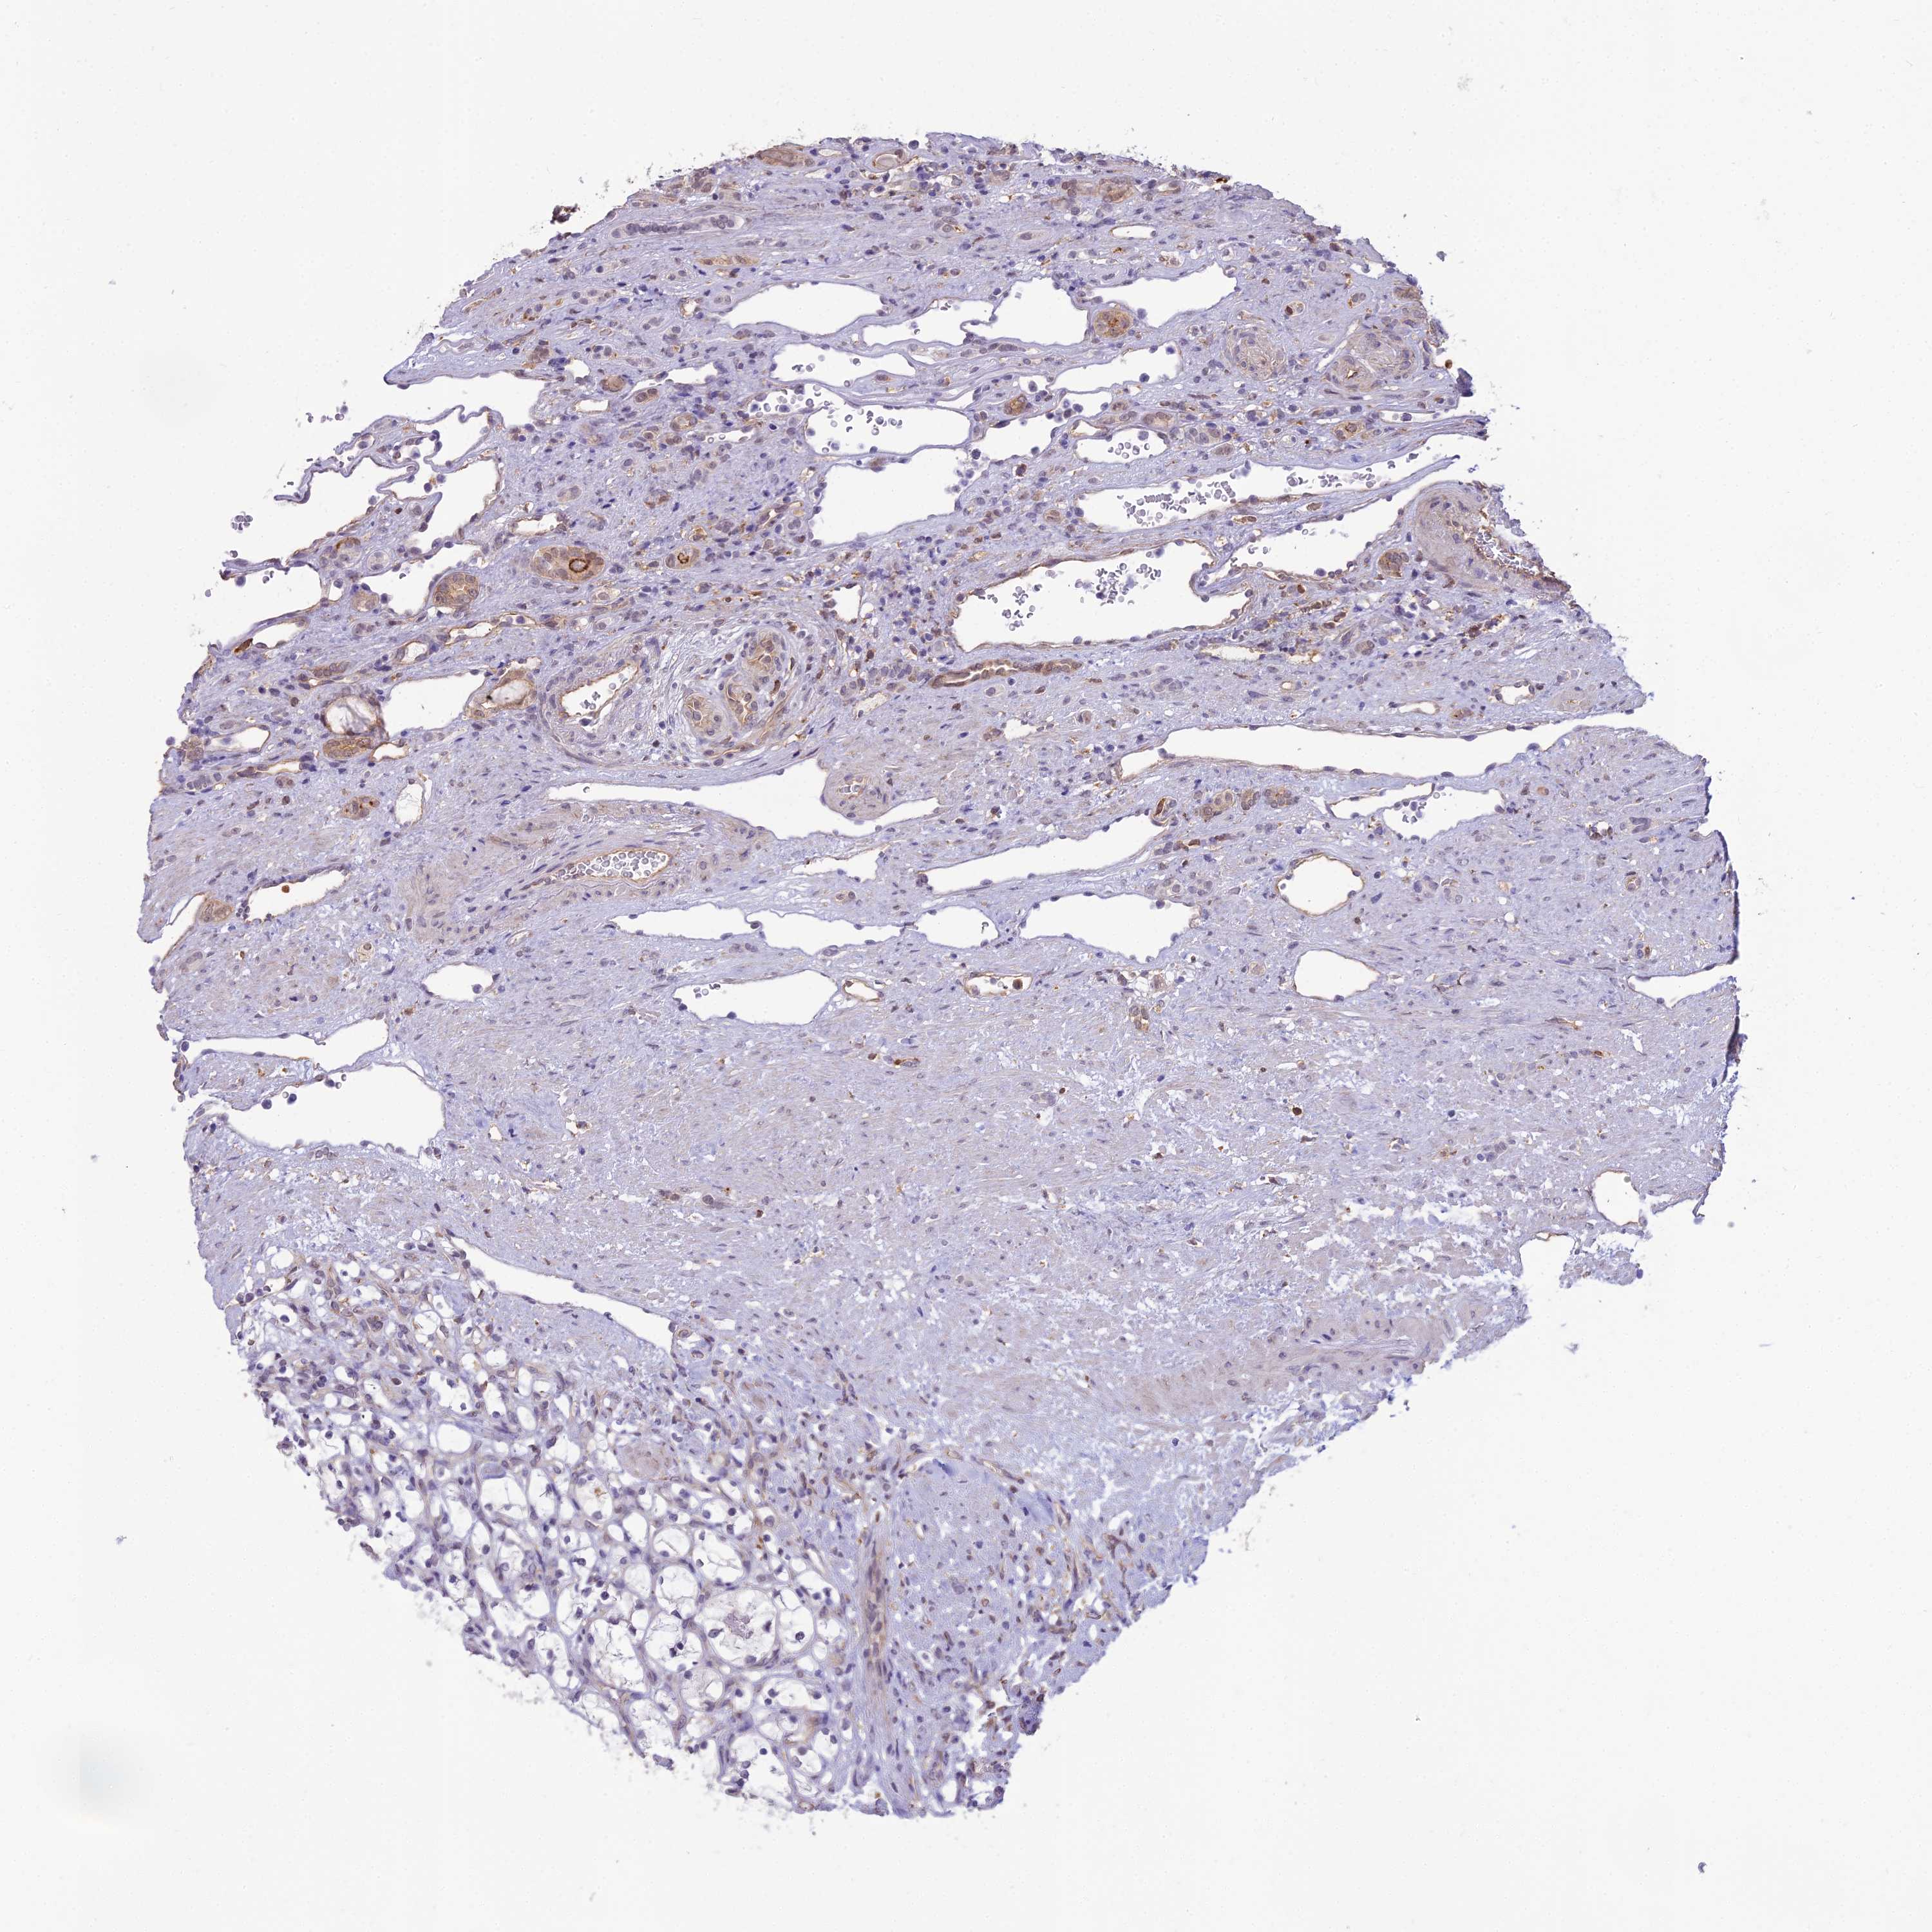

CANCER RENAL CANCER Show tissue menu

KICH TCGA KIRC TCGA KIRC VALIDATION KIRP TCGA PROTEIN RCC CPTAC PROTEIN EXPRESSION